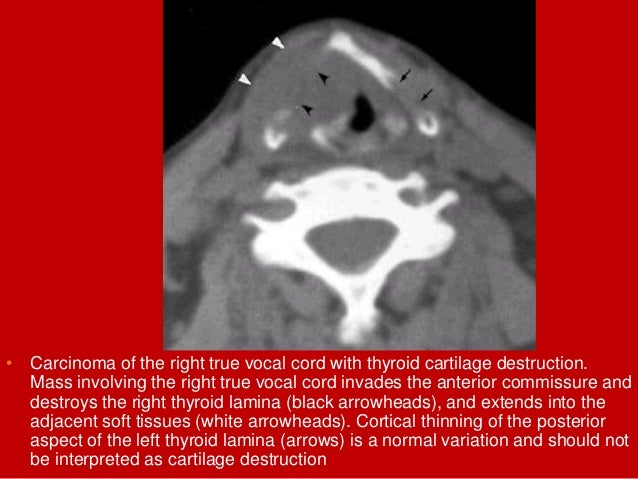

38. 38. • Carcinoma of the right true vocal cord with thyroid cartilage destruction. Mass involving the right true vocal cord invades the anterior commissure and destroys the right thyroid lamina (black arrowheads), and extends into the adjacent soft tissues (white arrowheads). Cortical thinning of the posterior aspect of the left thyroid lamina (arrows) is a normal variation and should not be interpreted as cartilage destruction